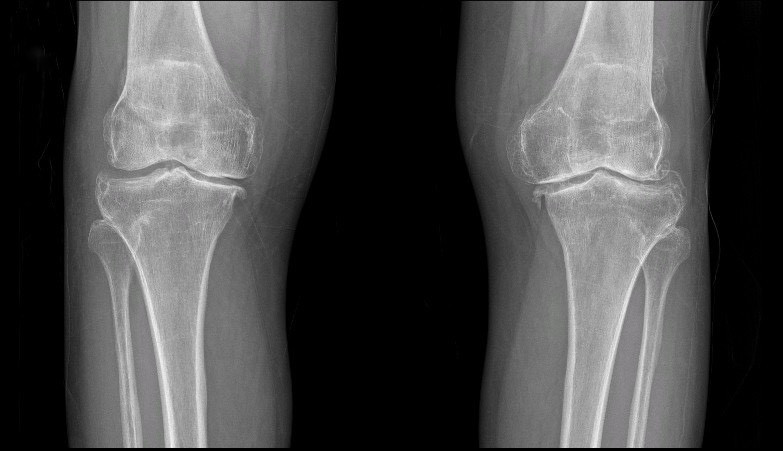

TS.BS Lê Quang Huy (Trưởng Đơn nguyên chấn thương chỉnh hình - BVĐK Hồng Ngọc) - bác sĩ trực tiếp thăm khám cho bà Liên chia sẻ: “Cả hai khớp gối của bệnh nhân bị thoái hóa giai đoạn IV kèm biến dạng vẹo trong rất nặng. Phần lớn lớp sụn khớp đã bị hao mòn và không còn nguyên vẹn, khe khớp giữa hai đầu xương hẹp đáng kể, xuất hiện nhiều gai xương. Điều trị bảo tồn bằng thuốc và các thủ thuật nội khoa hiện không còn hiệu quả nên tối ưu nhất là phẫu thuật thay khớp gối nhân tạo để khôi phục lại vận động cho bệnh nhân.”

| Hình ảnh thoái hóa khớp gối trên phim chụp Xquang |